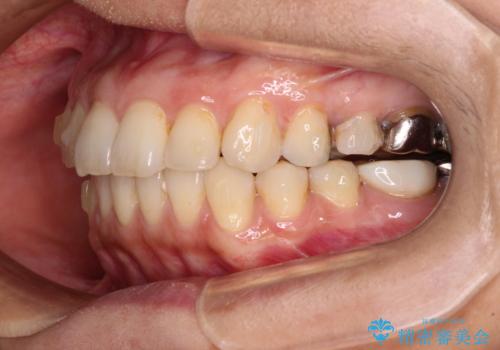

後戻りは軽微であったため、インビザライン・ライトにて歯列を整えました。

矯正治療後には、左下奥歯の症状がないことを確認し、セラミッククラウンにて補綴治療を行うこととしました。

矯正治療後のレントゲン写真では、根尖部に認められた病変(骨の溶けていた像)は消失していることが分かりました。